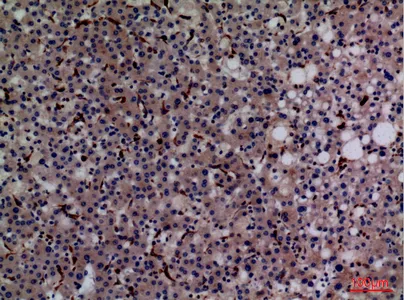

CD68 Rabbit Polyclonal Antibody

Cat: APRab08436

Size1:50μl Price1:$118

Size2:100μl Price2:$220

Size3:500μl Price3:$980

Size2:100μl Price2:$220

Size3:500μl Price3:$980